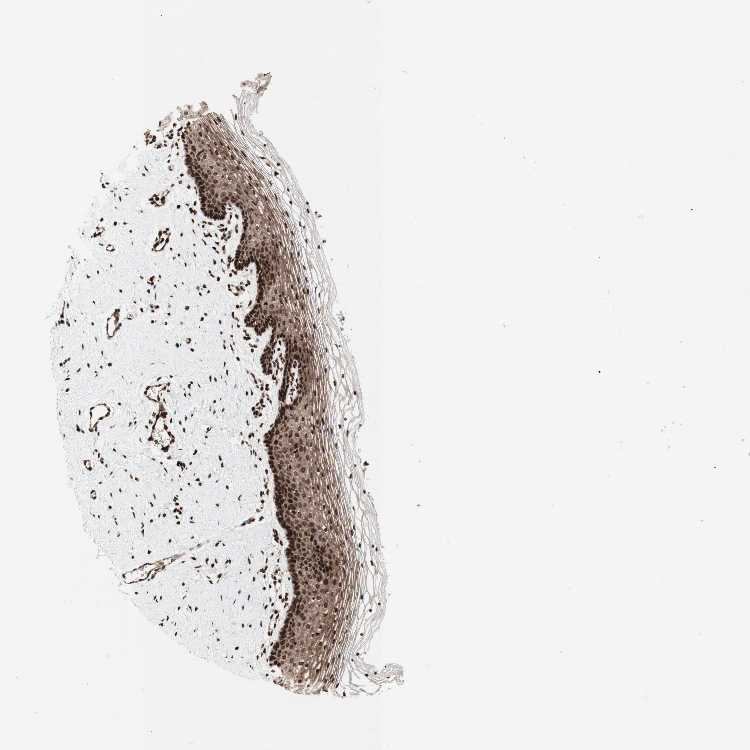

TISSUE PRIMARY DATA VAGINA Show tissue menu

VAGINA - Antibody stainingi

Antibody staining in the annotated cell types in the current human tissue is reported as not detected, low, medium, or high, based on conventional immunohistochemistry profiling in selected tissues. This score is based on the combination of the staining intensity and fraction of stained cells.

Each image is clickable and will lead to virtual microscopy that enables deeper exploration of all samples and also displays staining intensity scores, fraction scores and subcellular localization as well as patient and tissue information for each sample.

Antibody HPA036947Antibody HPA037363Antibody CAB012423

Squamous epithelial cells LowMediumHigh